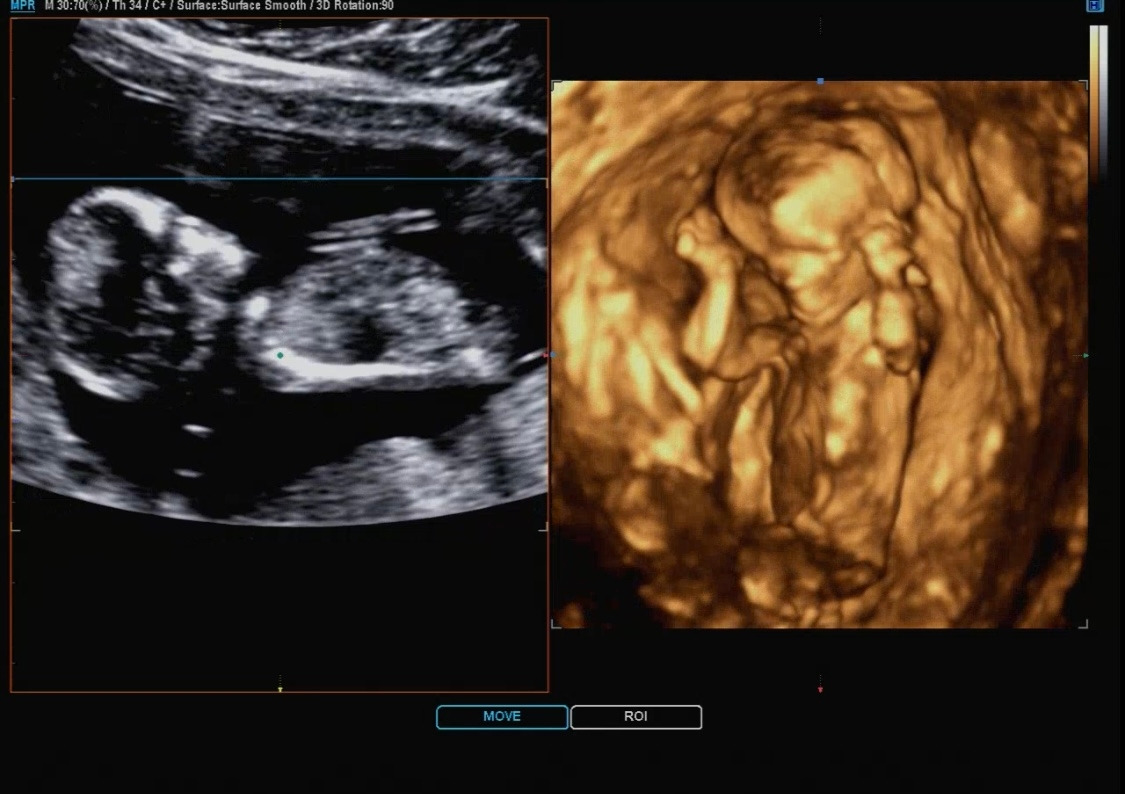

12주 입체초음파.jpg

입체 초음파는 다른 건 없고 이런 식으로 아가의 모습을 입체로 바꿔서 보여주는 것을 말한다. 하지만 아직은 아가의 모습이 정확하지 않아서 처음에는 어디가 어디인지 나는 구별하기가 정말 힘들었다.

선생님께서 계속 보이시죠~ 여기가 어디고 여기가 어디예요~라고 설명해 주시는데 처음에는 전혀 모르겠더라... 그렇게 계속 보다 보니 조금씩 아가의 모습이 나도 보이기 시작했다. 12주 차의 입체 초음파는 ㅎㅎ 크게 별게 없다.

아가가 움직일 경우 순간의 스샷을 여러 개 찍어서 입체를 만드는 것이기 때문에 더 어렵다고 한다. 다올이는 계속 움직이고 자세를 바꾸는 바람에 예쁘게 입체 초음파를 찍기는 어려웠지만 선생님께서 많은 노력을 해주셨다. 입체 초음파는 4장 정도 찍어주셨다. 4장 모두 다른 모습으로 찍혔다. 하나의 포즈는 나와 똑같이 하고 있어서 선생님과 같이 엄청 웃었다.